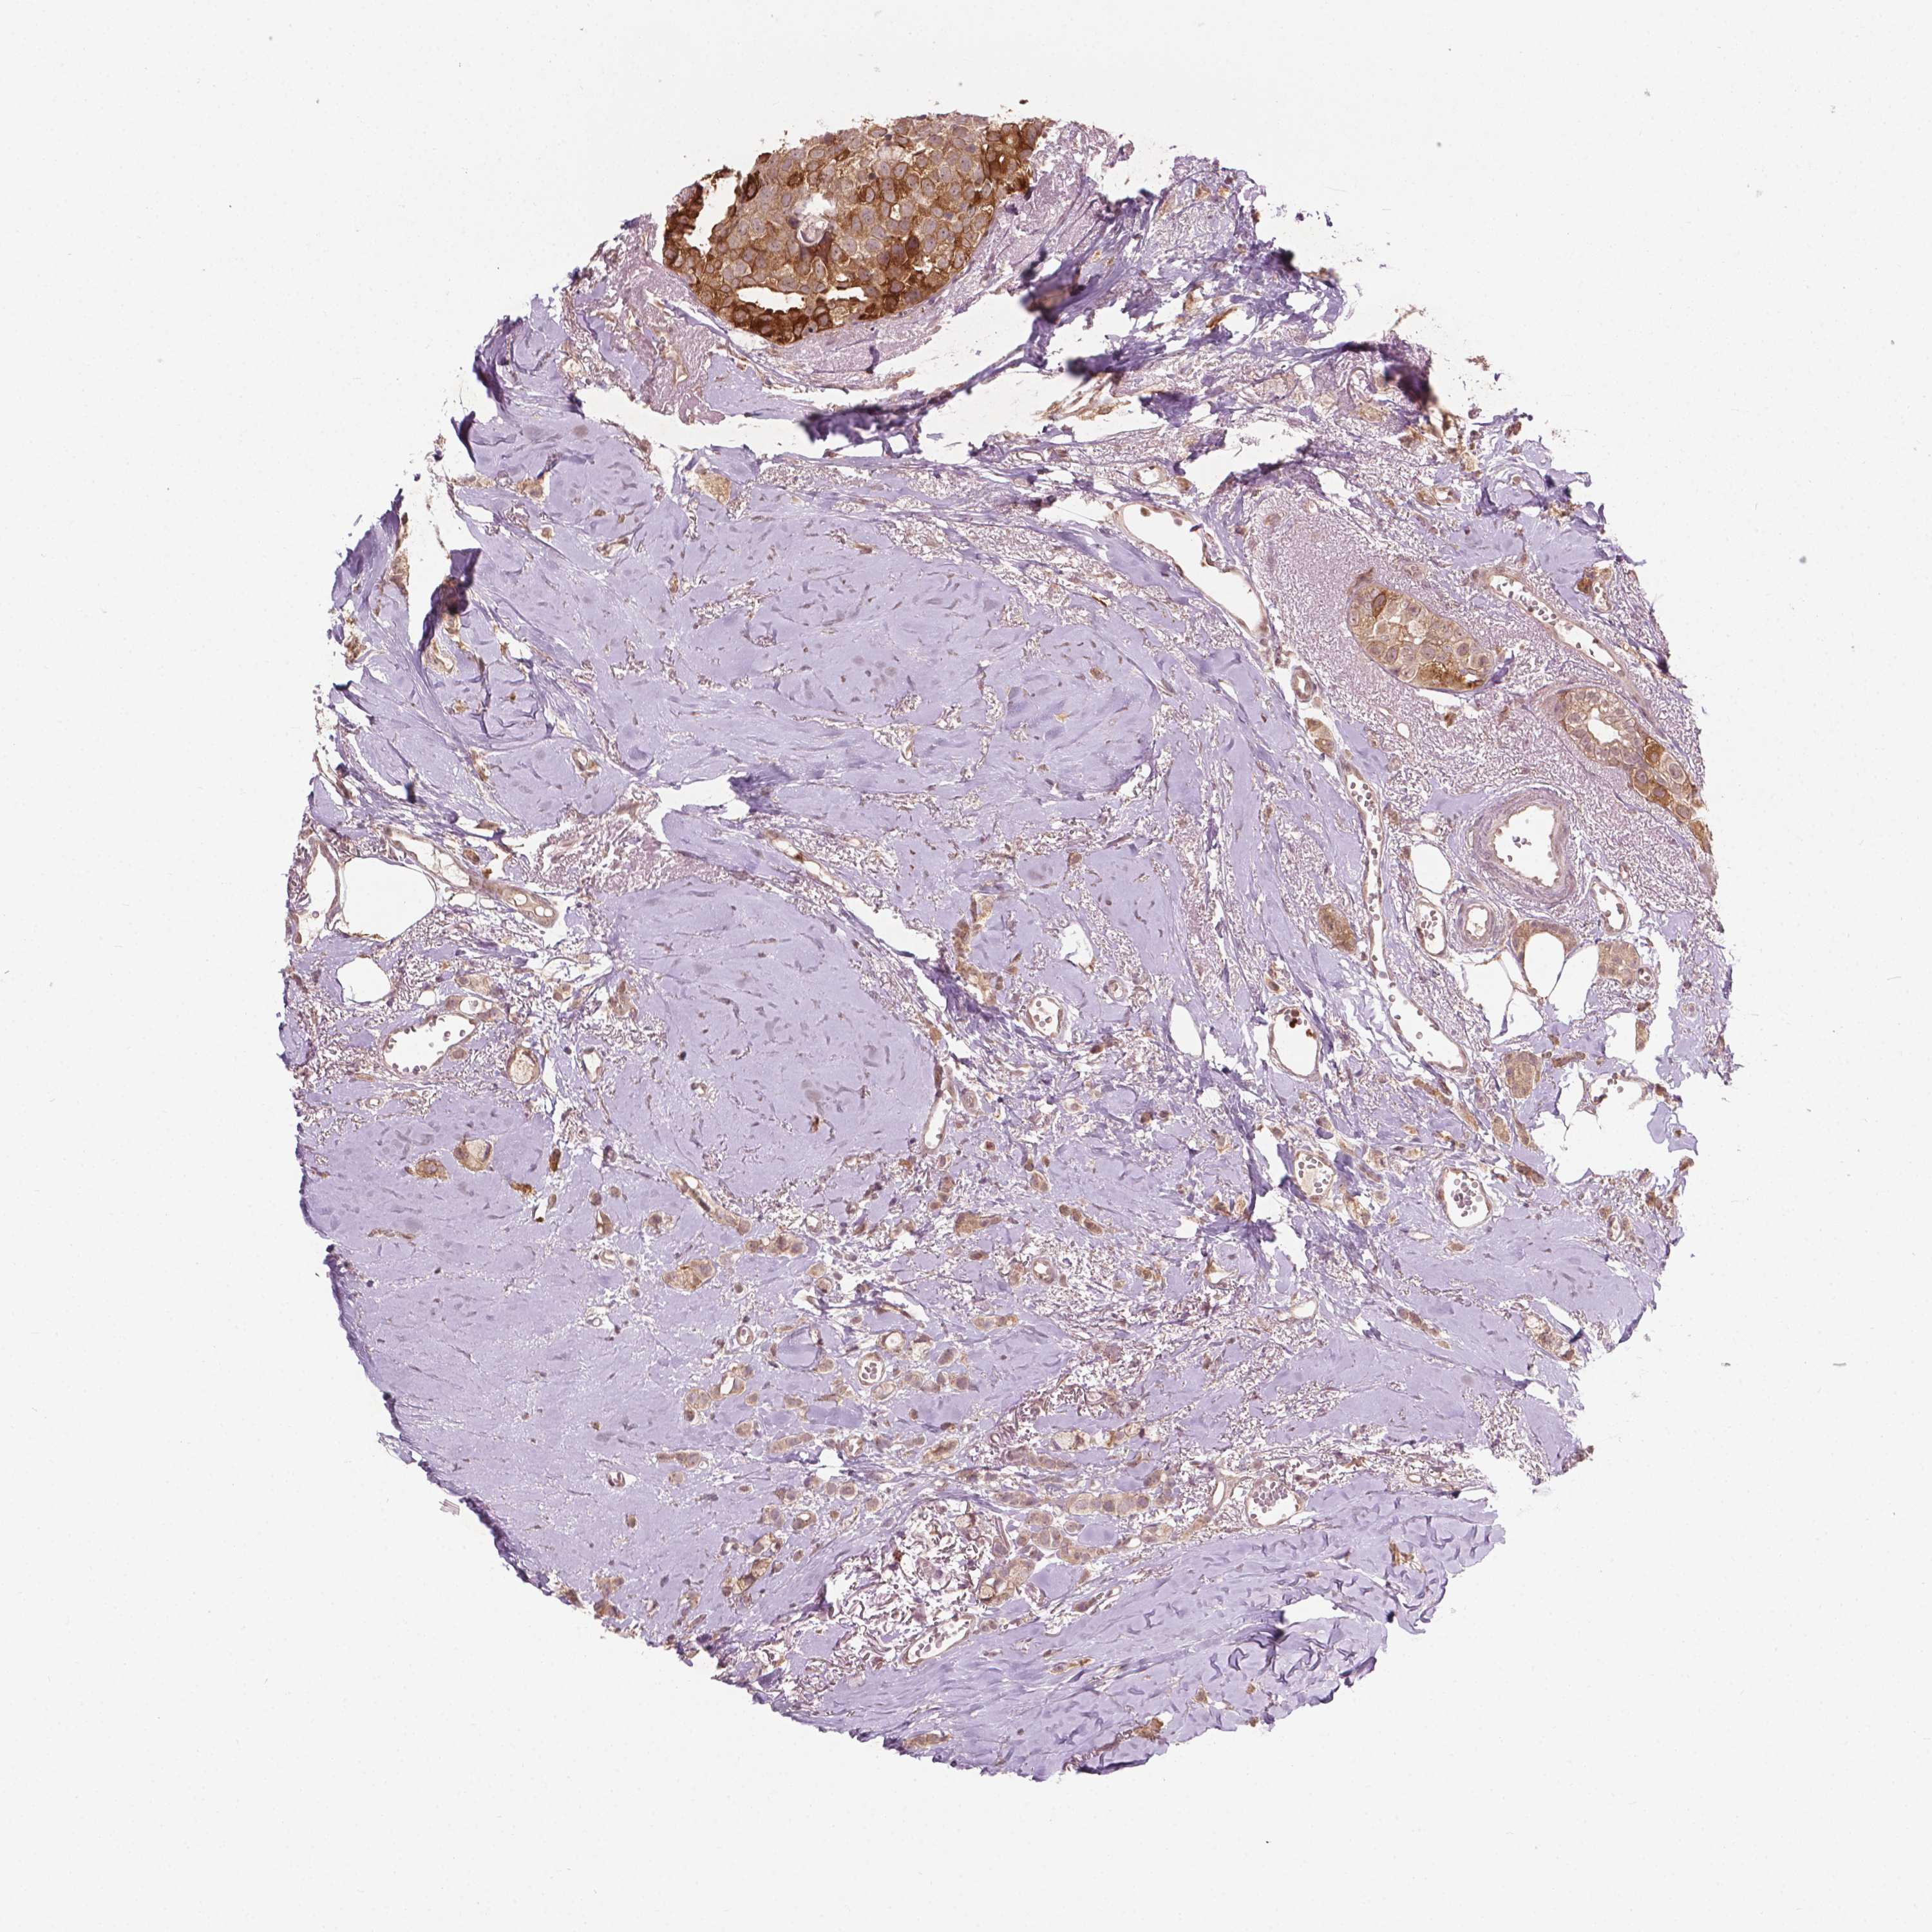

BRCA TCGA BRCA VALIDATION PROTEIN EXPRESSION

ANTIBODIES

AND

VALIDATION